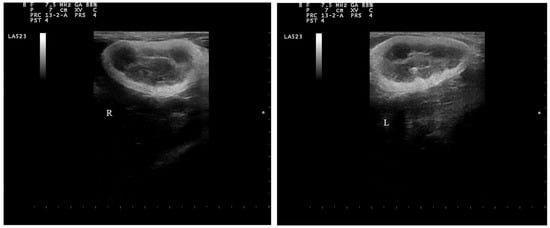

2.4. Doppler Examination